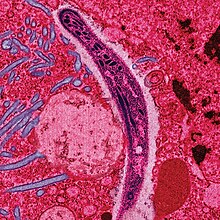

| False-colored electron micrograph showing a malaria sporozoite migrating through the mosquito midgut epithelial cell | |